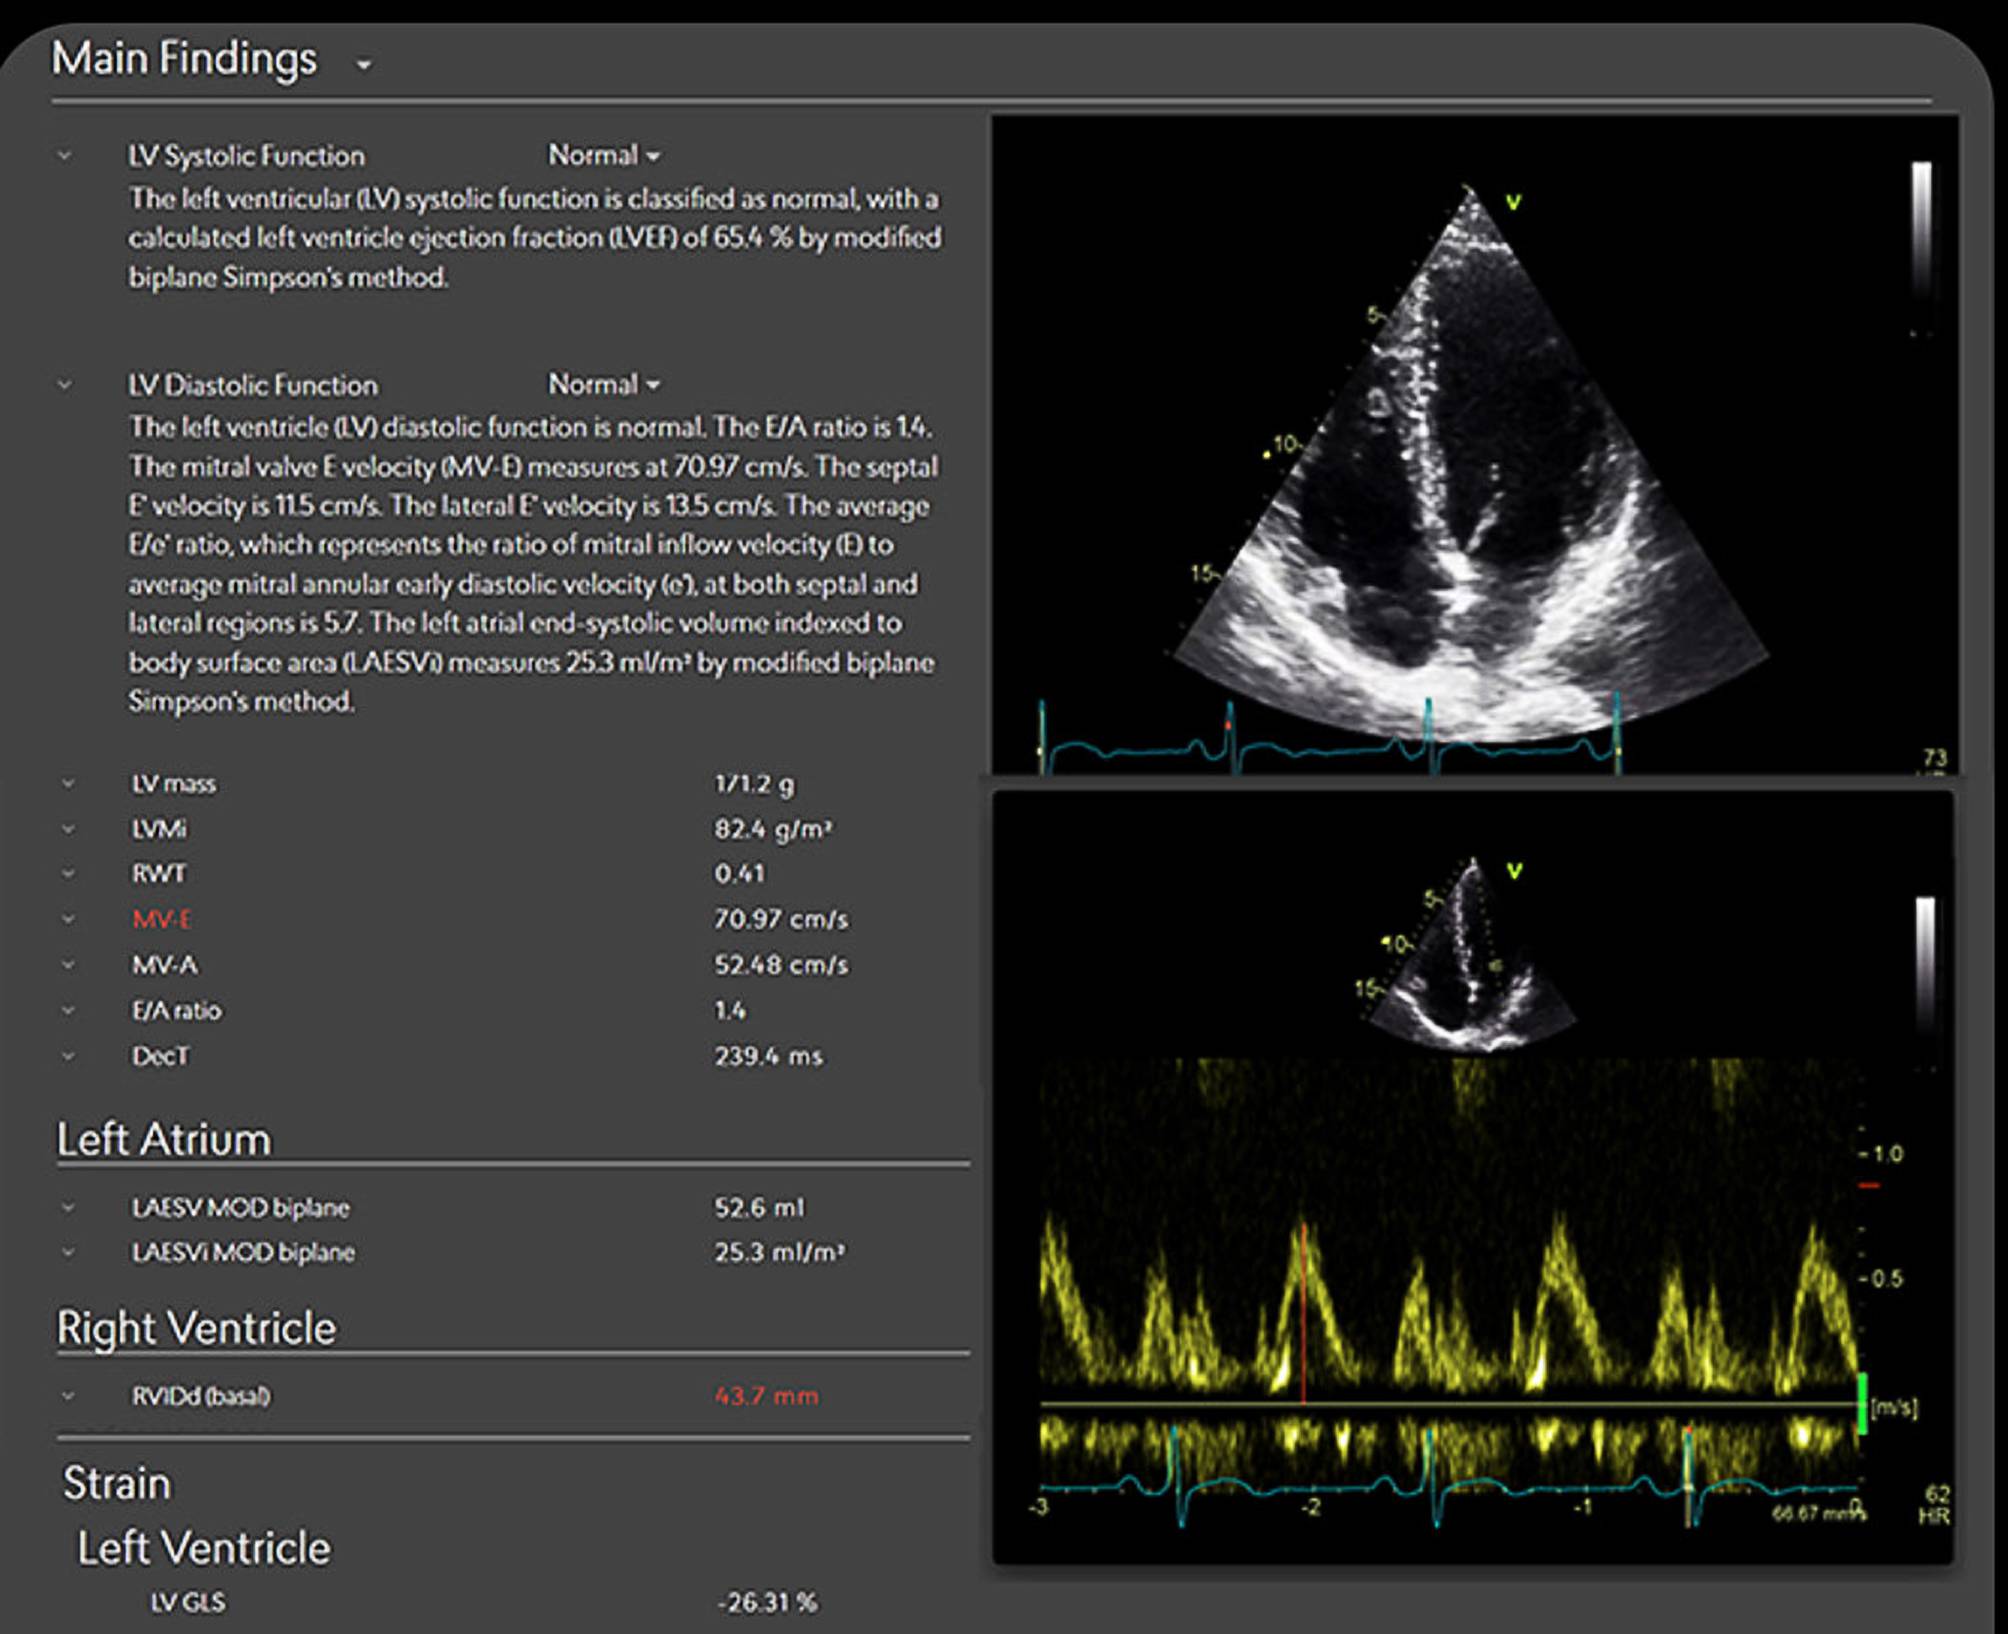

Transforming echocardiography with artificial intelligence

Us2.AI is a CE-marked, vendor-neutral software platform for automated analysis of TTE’s (Fig. 1). It integrates with stand...